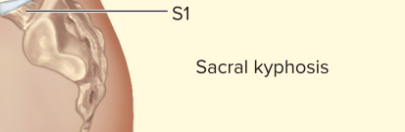

Sacrum

5 fused vertebrae (1 bone), posterior, curves outward toward back

Pelvic curvature

Kyphosis, concave anteriorly, curves outward